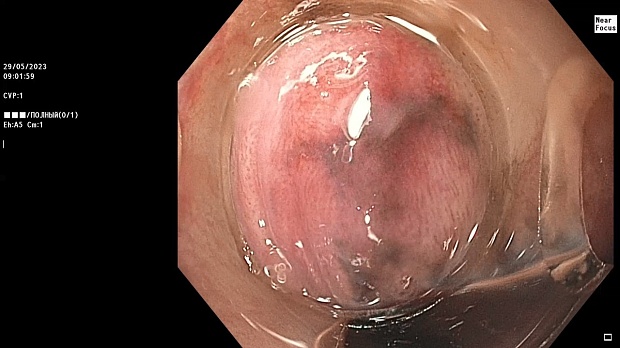

Иллюстрация №4: Микрофото. Г-Э х200. Сидероз пищевода

Эндоскопическое заключение было подтверждено данными патоморфологического исследования, согласно которому, в биоптате слизистой оболочки пищевода были обнаружены фрагменты поверхностных отделов слизистой оболочки, в субэпителиальной соединительной ткани которых обнаруживаются немногочисленные клетки с бурым пигментом в цитоплазме – картина сидероза (Рис.4)

Патолого-гистологическое заключение

В препарате мелкие фрагменты поверхностных отделов слизистой оболочки пищевода, в субэпителиальной соединительной ткани которых обнаруживаются немногочисленные клетки с бурым пигментом в цитоплазме. Опухолевого роста в пределах данного материала нет.